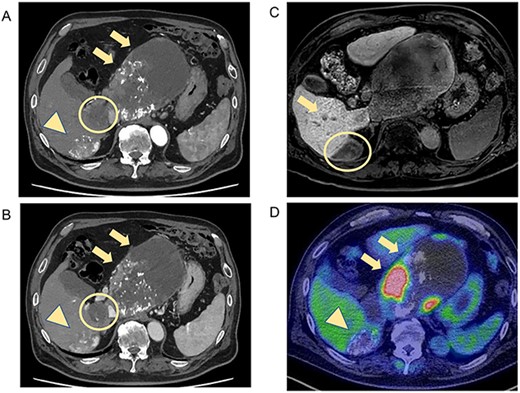

CT and MRI showed weakened stained areas of the S1 and S6/7 tumors with internal lipiodol deposition and poor enhancement. Positron emission tomography-CT showed no abnormal fluorodeoxyglucose accumulation suspicious for lymph node metastasis or distant metastasis (Fig. 2). The patient was evaluated as having stable disease in the Response Evaluation Criteria in Solid Tumors (RECIST) and a partial response in the modified RECIST.

CT and MRI after LEN plus TACE. Axial enhanced CT shows weakened stained areas of the tumors in S1 (A, B, arrow, circle) and S6/7 with internal lipiodol deposition and poor enhancement (A, B, arrowhead), with weakly enhanced areas at the margins that are suspected to be viable lesions. MRI reveals lesions with extensive internal hemorrhage because of treatment in S6/7 (C, circle) and S6 (C, arrow). Positron emission tomography-CT shows the mass lesions with abnormal accumulation in liver S1 (SUV max 11.7; D, arrow) and S6/7 (SUV max 4.2; D, arrowhead). S, segment; SUV, standardized uptake value.